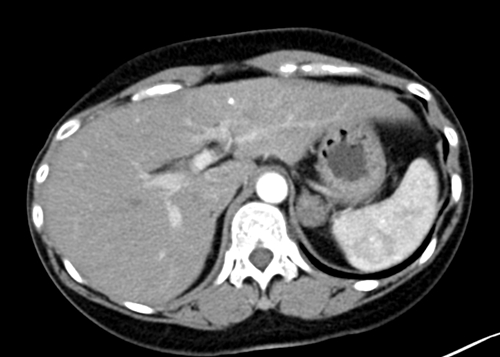

45岁的王女士(化名)常规体检行胸部CT检查,发现左肾上腺区占位。入院增强CT检查提示患者左侧肾上腺区占位性病变,动脉期明显强化。通过细致问诊和查体,泌尿外科何晓亮主任考虑其为嗜铬细胞瘤可能较大,并耐心地向患者及家属告之病情。考虑到该手术难度高,风险极大,术前准备时间长,泌尿外科组织开展了肾上腺肿瘤MDT,积极研讨病情,制定了完善的诊疗方案。经过充分术前准备,患者各方面指标均趋于平稳,何主任团队决定为其安排手术,摘除这颗困扰王女士的“定时炸弹”。

患者周女士(化名),因“左腰部酸胀不适4月”入院治疗。CT检查发现,患者左肾上腺占位性病变,进一步检查发现患者促肾上腺皮质激素(ACTH)被抑制,皮质醇节律消失。内分泌科会诊后行小剂量地塞米松试验检查后,初步考虑为库欣综合征。通过介入与血管外科团队肾上腺静脉采血(AVS)后,最终确诊患者为左肾上腺肿瘤导致的库欣综合征。经过充分术前准备,泌尿外科何晓亮团队成功为患者摘除了功能性肾上腺肿瘤。